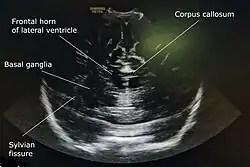

Technique

A 5 to 7.5 MHz probe is used to scan deeper structures in the brain. A 7 to 12 MHz probe is used for scanning superficial structures for detecting lesions between the brain and the skull, superior sagittal sinus thrombosis, cerebral oedema, and evaluating the structures of sulci and gyri.[4]

A water-based gel is applied to the infant's head, over the anterior fontanelle, to aid conduction of ultrasound waves. Ideally scans are performed during sleep or when the infant is calm. The operator then uses an ultrasound probe to examine the baby's brain, viewing the images on a computer screen and recording them as necessary.

A standard cranial ultrasound examination usually involves recording of approximately 11 views of the brain from different angles, six in the coronal plane and five in the sagittal and parasaggital planes.[7] This allows all parts of the ventricles and most of the rest of the brain to be visualised.